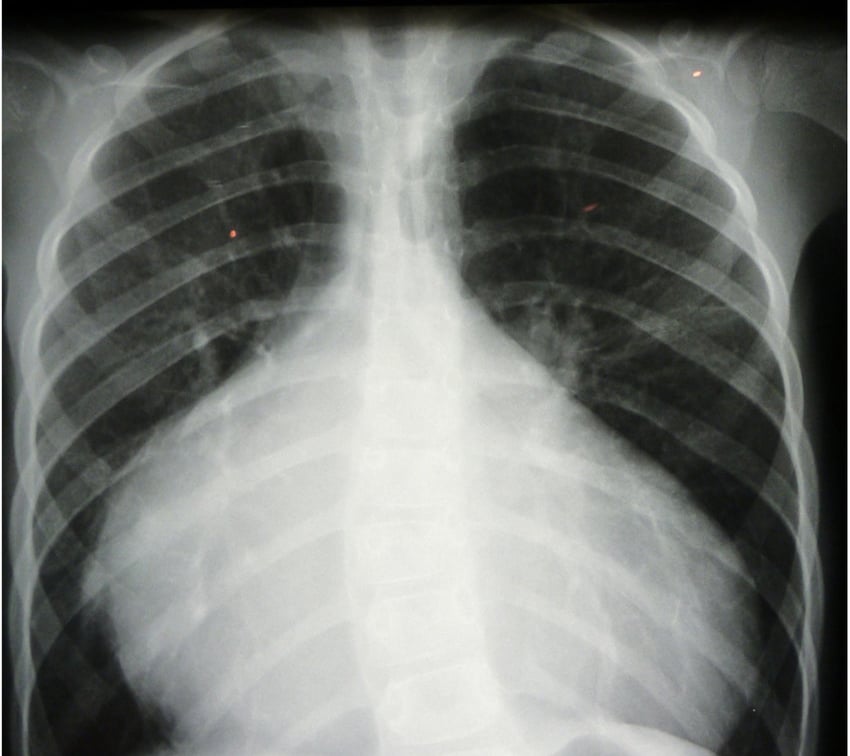

En muchos casos, la cardiomegalia no presenta síntomas visibles y se detecta de forma incidental mediante estudios como radiografías de tórax.

El diagnóstico inicial se realiza mediante estudios de imagen como radiografía de tórax, ecocardiograma, resonancia magnética o tomografía, acompañados de evaluación funcional cardiaca.